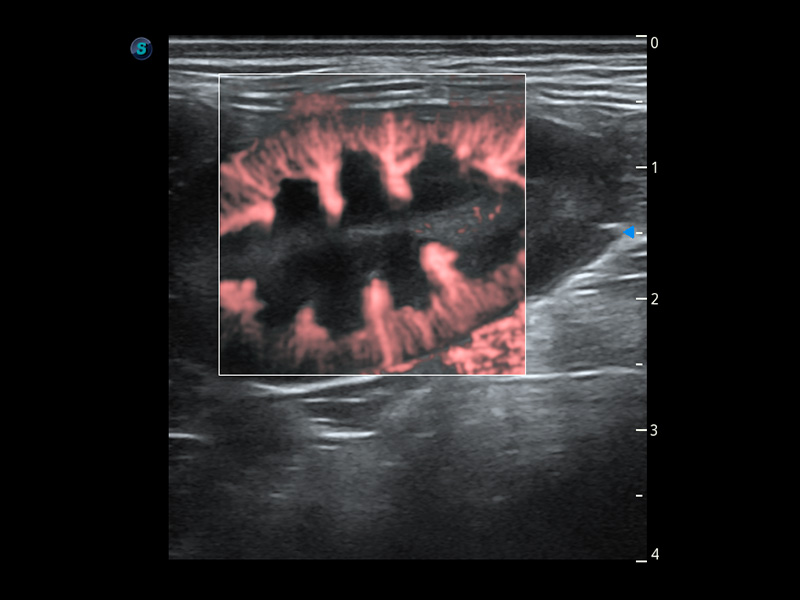

ProPet 60 作為一款高端臺式動物超聲設備,為動物醫(yī)生的日常診斷提供了一系列貼合動物臨床需求、解決臨床實際問題的高級成像功能。憑借全系列高清探頭,滿足醫(yī)生對腹部、心臟、生殖、淺表、肌骨等成像的所有需求,切實幫助您提升檢查效率,提高診斷信心。

動物是人類最親密的朋友和最值得信賴的伙伴。開立醫(yī)療也一直致力于探索動物專用的超聲影像解決方案。 全新推出的ProPet系列,是開立在動物超聲影像智能化、專業(yè)化、精準化的一次跨越式革新。動物不能用言語來表述自己的不適,通過超聲影像,ProPet系列搭建了動物醫(yī)生與不同物種溝通的“橋梁”,為動物醫(yī)生注入了“治愈之力”。